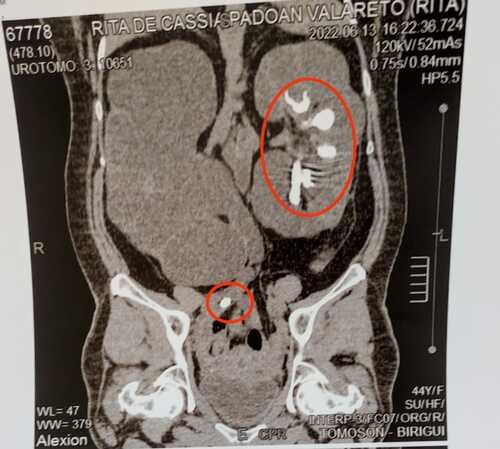

Olá! Meu nome é Cássia e a 1 ano atrás descobri que tenho pedras nos rins, fiz os exames e constou que meu rim direito estava comprometido já o esquerdo restou 50%, logo iniciei a vakinha para conseguir o valor restante dos exames, assim irei fazer os testes necessários para dar início ao tratamento, que no caso a cirurgia custa em torno de 25 mil reais, por conta disso preciso da colaboração de vocês meus amigos. Tentamos ajuda de todos os lados, entre políticos e pessoas responsáveis por ONGS logo sem êxito, tentamos também pelo SUS porém para conseguir vaga iria demora cerca de 3 anos no mínimo para começar o tratamento e preciso de início imediato, dentro de 6 meses meu único rim irá paralisar. Além de todos estes problemas citados acima já tive 2 AVCs, tenho diabetes tipo 2 e pressão alta.Peço a colaboração de todos, desde já agradeço de coração.